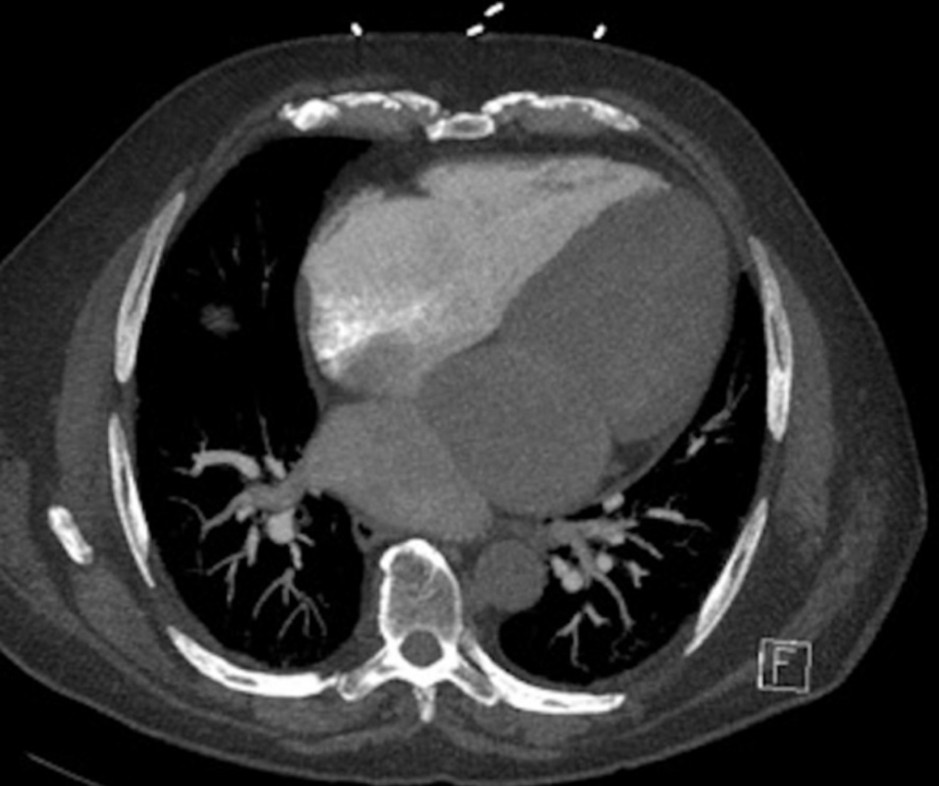

Caso clinico 1

Donna di 41 anni con dispnea ingravescente, episodi sincopali e recente fibrillazione atriale. Ecocardiogramma dubbio per stenosi mitralica.

Quale meccanismo spiega la dilatazione delle vene polmonari in questo caso?

- Insufficienza mitralica funzionale

- Aumento della pressione nel compartimento prossimale dell’atrio sinistro

- Ridotta contrattilità ventricolare sinistra

- Shunt destro-sinistro

- Aumento della compliance venosa

Risposta corretta: B

COMMENTO

Nel car triatriatum, la camera prossimale riceve le vene polmonari ma è separata dalla valvola mitrale.

Se la fenestrazione è piccola:

- si crea un ostacolo al deflusso

- ↑ pressione nella camera prossimale

- trasmissione retrograda → ipertensione venosa polmonare

Questo spiega:

- dilatazione delle vene polmonari

- sintomi simili a stenosi mitralica